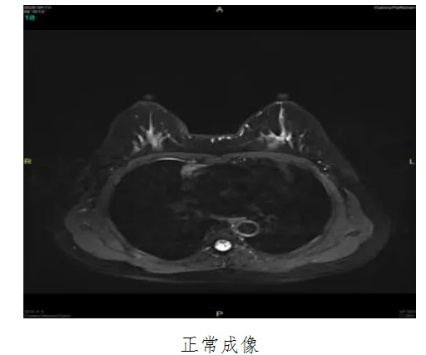

乳腺癌是我国近几年来发病率增速最快的癌症之一,严重危害女性的身心健康。如果能够早期发现并及时治疗,患者5年生存率可达70%。而磁共振乳腺成像的优势恰恰在于早发现,其对于乳腺癌早期诊断具有重要临床价值。我院超导1.5T磁共振已引进乳腺线圈,乳腺磁共振扫描现已为常规检查及体检项目,填补了安达医疗的空白。